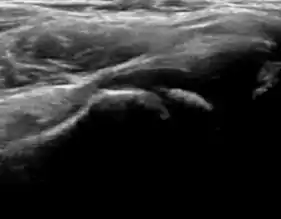

During childhood, ultrasound is a quick method to assess hip pain and quite often may be used to avoid use of irradiating techniques, such as radiography or CT. Ultrasound allows evaluation of joint effusion, synovial thickening and neovascularity, the bone/cartilage contour, and the femoral head-neck alignment. Although sonography is extremely sensitive in detecting increased synovial fluid, it is nonspecific and cannot be used with accuracy to determine the type of fluid. Transient synovitis of the hip, despite being the most frequent cause of pain in children between 3 and 10 years, remains a diagnosis of exclusion. It usually shows anechoic fluid, but echogenic fluid can also be found. The effusion is considered pathologic when it is measured at >2 mm in thickness. The differential diagnosis is wide, including osteomyelitis, septic arthritis, primary or metastatic lesions, LCPD, and SCFE. Discrimination from septic arthritis is challenging, often requiring joint aspiration. In septic arthritis, US is able to demonstrate a hip joint effusion, synovial thickening, and cartilage damage, although the appearances are nonspecific.[1]

A step between the head and the physis can be detected in children with SCFE, while abnormalities in the femoral head contour may suggest the presence of LCPD. In both cases, radiographs are mandatory to confirm diagnosis and severity (Figure 12).[1]

Figure 12:

Normal ultrasound appearance of the femoral head-neck junction.

Joint effusion in transient synovitis of the hip.

Flattening of the femoral head in a patient with Perthes disease.

Step in the femoral head-neck junction in a patient with SCFE.